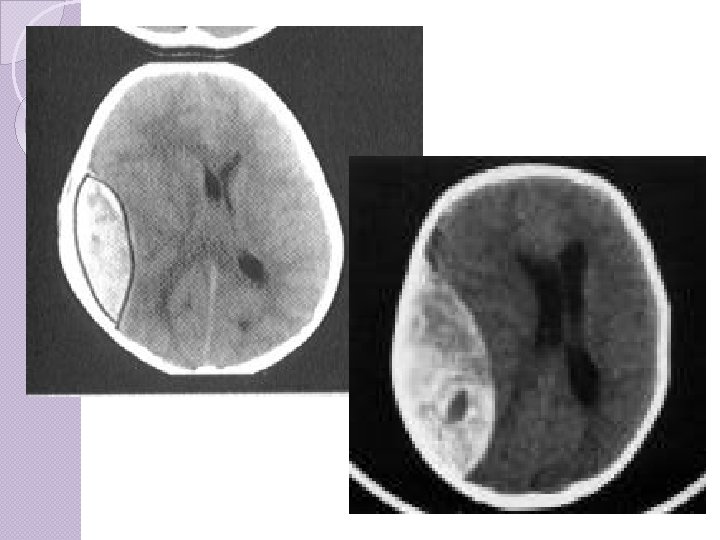

CLASSIFICAÇÃO Hematomas epidurais ◦ Osso e dura-máter ◦ Lente biconvexa, temporal ou têmporo-parietal, ◦ Ruptura da artéria meníngea média, causada por uma fratura. ◦ Tto precoce melhor prognóstico. ◦ Sintomático, > 1 cm, fossa posterior ◦ Clínica: intervalo lúcido seguido de “fala e morre”.

Hematomas Epidurais Ou extradurais ocorrem mais comumente por fratura da porção escamosa do osso temporal, em cuja face interna corre (em um sulco) a artéria meníngea média. Uma lesão desta causa um hematoma entre o osso e a dura-máter, de formação rápida, porque a pressão no vaso é arterial. Como a dura é aderida ao osso, os hematomas epidurais são circunscritos e arredondados. Forçam o lobo temporal em direção medial e provocam hérnia de uncus.

CLASSIFICAÇÃO Hematoma ◦ ◦ ◦ ◦ subdural: Mais freqüente que hematoma epidural Veia entre o córtex cerebral e o seio venoso. Recobrem toda a superfície do hemisfério. Comprometimento cerebral mais grave Prognóstico mais reservado que epidural Tto precoce, se sintomático Atraso maior que 4 hs: Mortalidade 59 69%;

Hematoma subdural A velocidade de formação do hematoma é variável de horas a dias. Inicialmente o sangue se coagula, mas vai lentamente se fluidificando por ação de fibrinolisinas. Os hematomas subdurais agudos podem causar hipertensão intracraniana elevada e hérnias. Além do tipo agudo, os hematomas subdurais podem ser crônicos, isto é, desenvolver-se lentamente, ao longo de semanas, após traumas pequenos esquecidos pelo paciente e desconhecidos familiares. São comuns em idosos e podem ser bilaterais